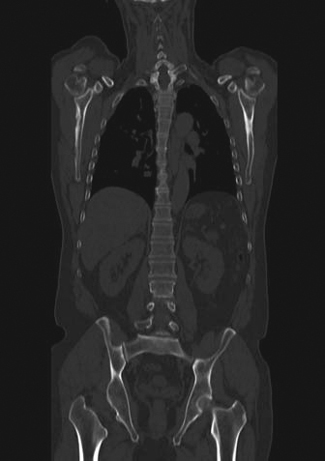

Tumor mesenquimal fosfatúrico

La osteomalacia oncogénica es un síndrome paraneoplásico caracterizado por dolor óseo y muscular, pérdida de densidad mineral ósea, marcada disminución del nivel plasmático de 1,25 dihidroxicolecalciferol, hipofosfatemia e hiperfosfaturia (Figura 13). La causa puede ser un tumor mesenquimal oculto que secreta una hormona llamada factor de crecimiento fibroblástico-23 (FGF-23), que pertenece a una clase de factores u hormonas conocidos como fosfatoninas41,42. Puede darse también en asociación con otras enfermedades tales como: cáncer de próstata, cáncer de células pequeñas, neurofibromatosis, cánceres hematológicos, síndrome del nevus epidérmico y displasia fibrosa poliostótica. El tumor mesenquimal, desde el punto de vista histológico, puede ser parecido a un variado número de neoplasias muchas de ellas benignas (hemangiopericitomas, hemangiomas, sarcomas, fibromas osificantes, granulomas, tumores de células gigantes y osteoblastomas)43. La resección quirúrgica del tumor es generalmente curativa. Sin embargo, muchos de estos tumores son pequeños y de ubicación inusual por lo que su localización suele ser muy difícil. Pueden aparecer en huesos o tejidos blandos, en cualquier parte del cuerpo. PET/CT con F18-FDG es el método más sensible para su localización, sin embargo, de baja especificidad debido a la captación de F18FDG por lesiones no neoplásicas tales como reparación de fracturas óseas, que son muy frecuentes en estos pacientes. Debido a que numerosos tumores mesenquimales expresan receptores de somatostatina, tales como tumores óseos, vasculares y perivasculares (osteosarcomas, tumor de células gigantes, angiosarcomas, hemangiopericitomas), sarcomas sinoviales, histiocitomas y tumores de origen muscular (leiomiomas, leiomiosarcomas y rabdomiosarcomas)44, el uso de trazadores para receptores de somatostatina es útil en estos pacientes. Tanto el SPECT con In111-pentatreotide como el PET con Ga68-DOTATATE u otros análogos han sido usados exitosamente para localizar estos tumores (Figura 14). La adición de imágenes estructurales (SPECT/CT y PET/CT) mejoran aún más el rendimiento del examen. Particularmente en estos casos es necesario realizar un examen de cuerpo total, desde el vértex craneal hasta los pies, incluyendo las extremidades superiores completas, debido a que el tumor puede estar en cualquier parte. Por el momento no hay estudios que comparen el rendimiento del In111-Octreoscan con PET con Ga68-octreotide.